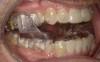

Fig 8. The appliance worn during treatment, anterior view (Fig 8), right side view (Fig 9), left side view (Fig 10), and upper arch view (Fig 11).

Figure 8

Fig 9. The appliance worn during treatment, anterior view (Fig 8), right side view (Fig 9), left side view (Fig 10), and upper arch view (Fig 11).

Figure 9

Intraoral scans were taken to document the patient's entire palate and bite registration. Scans were sent to the clinical team for the fabrication of a clear aligner/sleep appliance for the patient to wear; the chosen appliance fits over clear aligners, regardless of the tray number the patient may need (Figure 7 through Figure 11).

After the appliance was delivered, additional photographs were taken with the camera to ensure that the appliance was delivered as intended, to document the case, and to show the patient the ideal fit of the appliance in his mouth as instructions were reviewed with him.